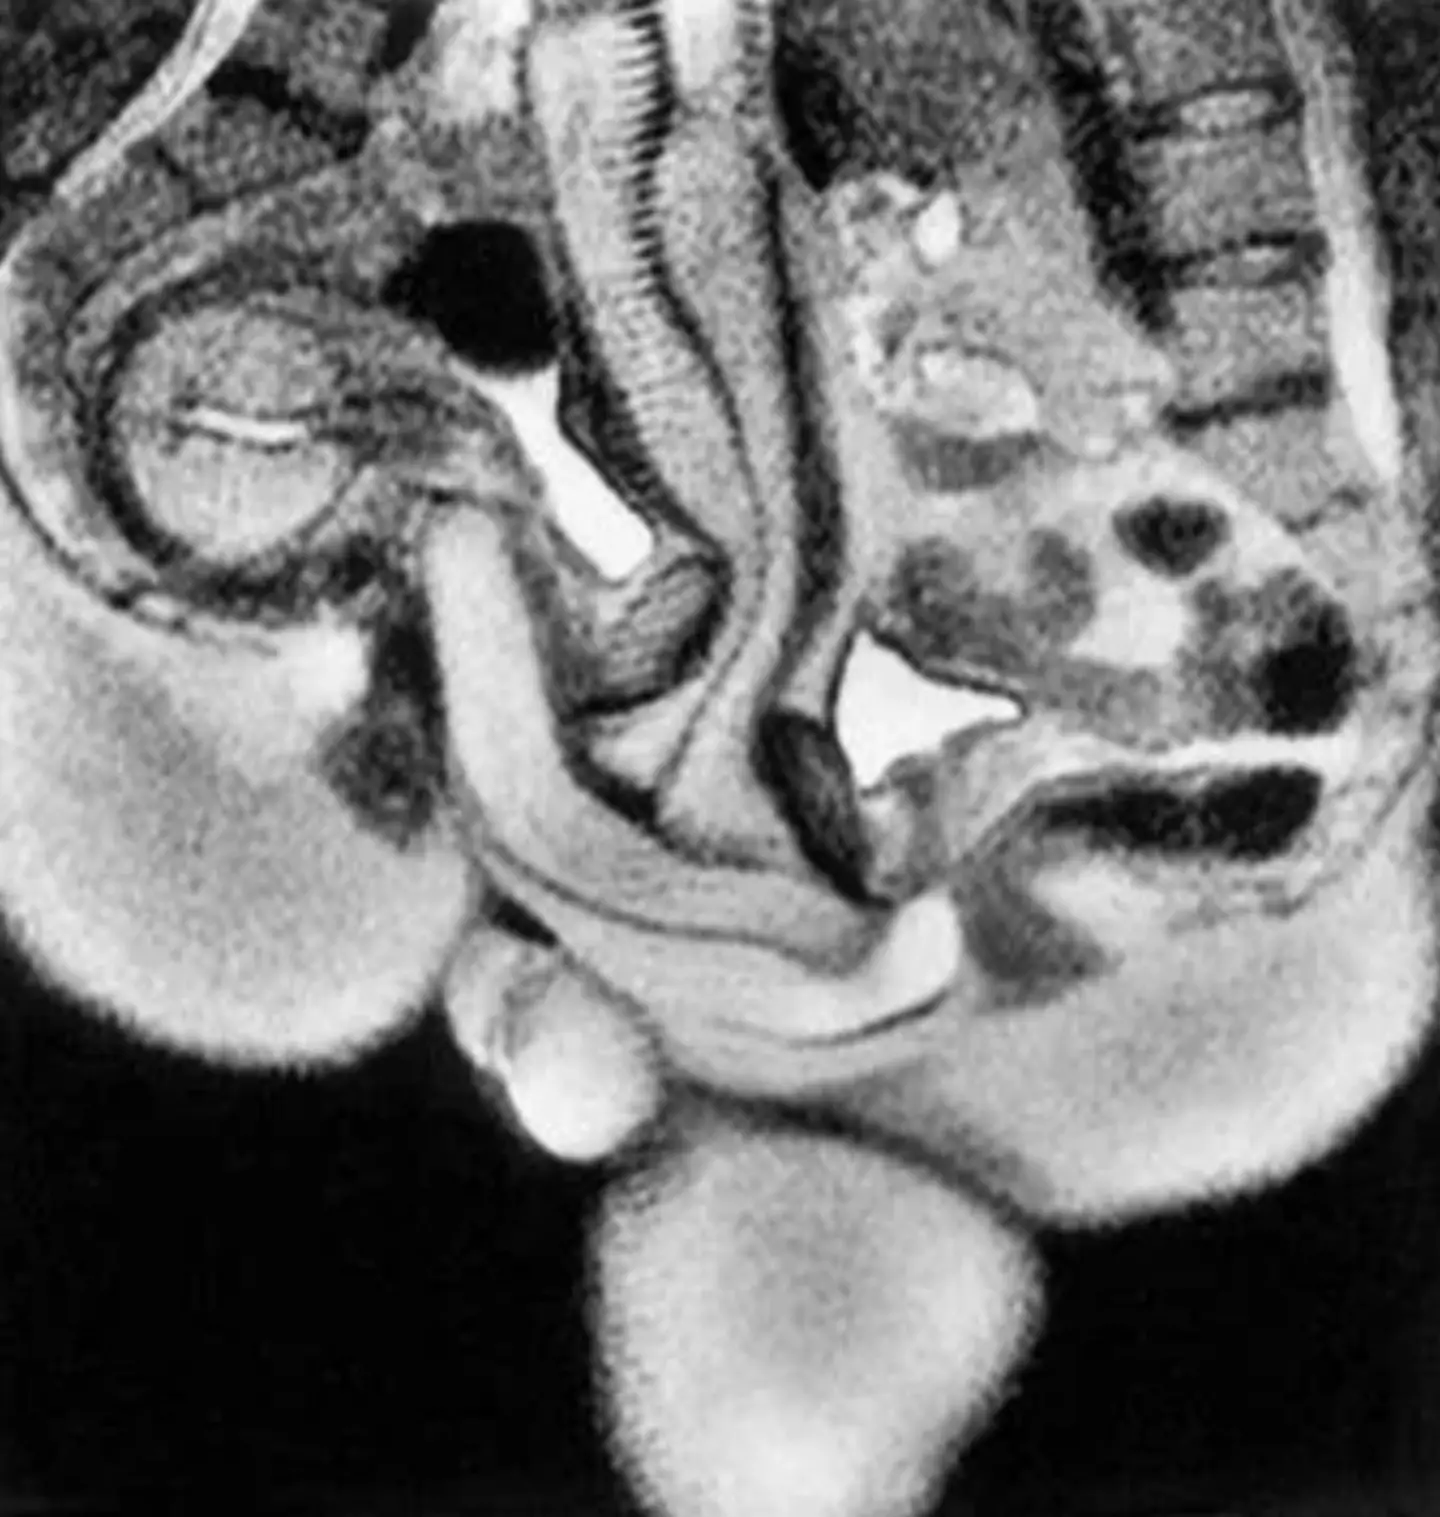

The images, if you want to see them, show two spines as well as genitalia and show exactly how the male and female bodies fit together during sex. If you wanted to study it more closely, there's even a handy key: P=penis, Ur=urethra, Pe=perineum, U=uterus, S=symphysis, B=bladder, I=intestine, L5=lumbar 5, Sc=scrotum.

The photographs, taken during the missionary position, were also useful scientific studies as they showed that the penis isn't straight during in sex but actually curved to fit the natural curve of the vagina.

Also, scientists had previously thought that the uterus expanded during sex but this was proven that despite female arousal, it doesn't appear to get any bigger.